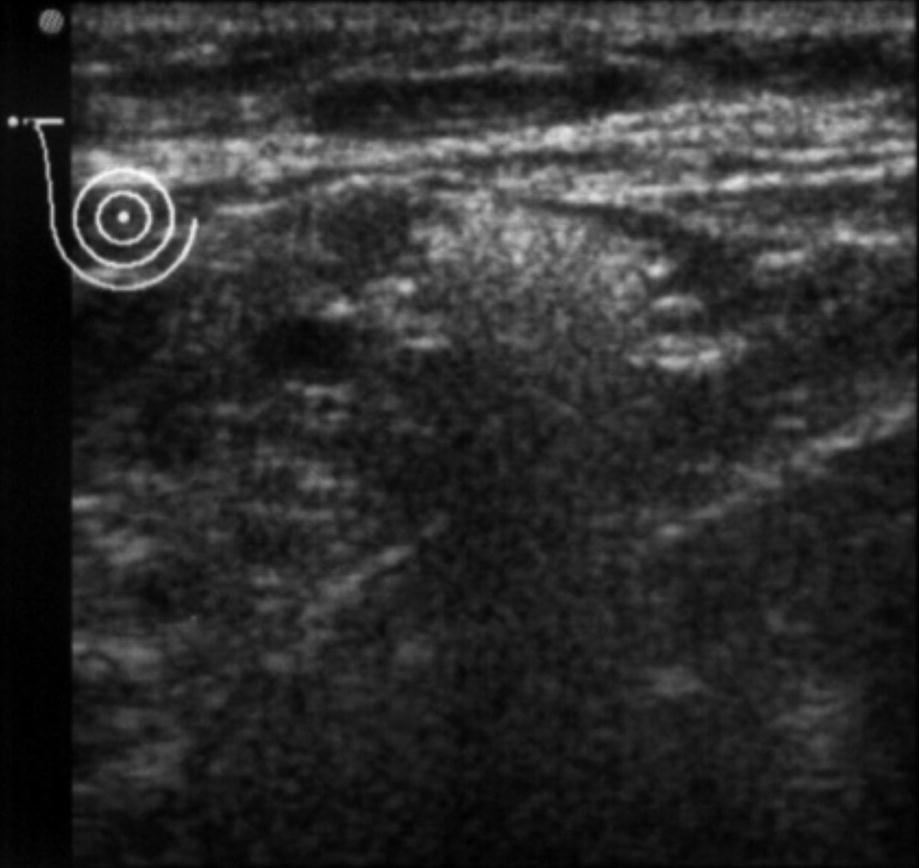

Ultrasound reveals siliconoma nodules and the classic “snowstorm” appearance. (Courtesy of Dr. Román Rostagno)

Ultrasound reveals axillary lymph node infiltration by silicone within the hilum. (Courtesy of Dr. Román Rostagno)